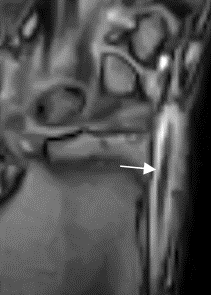

Fig 94 C. Tenosinovitis de Quervain.

RM coronal en GE. Líquido rodeando los tendones del 1º compartimiento extensor, por tenosinovitis de Quervain.